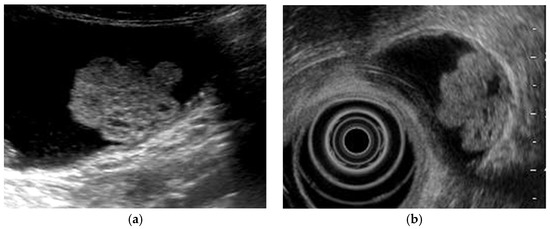

Figure 6. Cystic structures (anechoic spots) corresponding to cystically dilated cancerous glands. (a) High-frequency transducer (8 MHz) and (b) EUS (12 MHz) showed irregularly shaped cystic lesions of various sizes corresponding to cystically dilated cancerous glands (GBC concomitant with pancreatobiliary maljunction case).